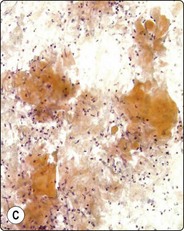

Sialadenitis (Figs 4.25, 4.26)

image image

Fig. 4.25 Chronic sialadenitis

Fragments of epithelium mainly of ductal origin showing mild reactive atypia and some squamous metaplasia; fragments of fibrous stroma; relatively few chronic inflammatory cells. (A, MGG, IP; (B, Pap, IP).

Fig. 4.26 Chronic sialadenitis

(A) Sheet of ductal epithelium showing squamous metaplasia. This could be mistaken for low-grade mucoepidermoid carcinoma or other low-grade neoplasm (Pap, HP); (B) Corresponding histology, most acinar epithelium replaced by fibrous tissue with patchy inflammatory cell infiltration, and prominent ducts showing mild reactive atypia and squamous metaplasia (H&E, IP).

Criteria for diagnosis

Purulent aspirate in acute, infective sialadenitis,

Scanty material of mainly ductal epithelial cells, few acinar cells in chronic sialadenitis,

Sheets of ductal epithelium showing regenerative atypia and/or squamous metaplasia,

Variable numbers of inflammatory cells, usually few in chronic sialadenitis,

Fragments of fibrous stroma.

Purulent material aspirated from a tender, swollen gland suggests infective sialadenitis. Smears contain a mixed population of numerous neutrophils, foamy degenerate cells and endothelial cells. The swelling should subside after antiinflammatory treatment.

Most cases of chronic sialadenitis referred for FNB are in a late stage when interstitial fibrosis and atrophy of acinar tissue have taken place. The inflammatory cell infiltration may have subsided and may be sparse and patchy. FNB smears are therefore often scanty, mainly of ductal epithelial cells associated with only few acinar cells and inconspicuous inflammatory cells. Fragments of fibrous stroma are often present (Fig. 4.25). Crystalloids may be present in the aspirate.95 Regenerating ductal epithelium in chronic sialadenitis may undergo squamous metaplasia and may appear atypical (Fig. 4.26). Mucus-like material from dilated ducts may be present. This may be suggestive of a neoplastic lesion or even of malignancy, mainly low-grade mucoepidermoid tumor. Multiple sampling and clinical correlation usually solves the problem.